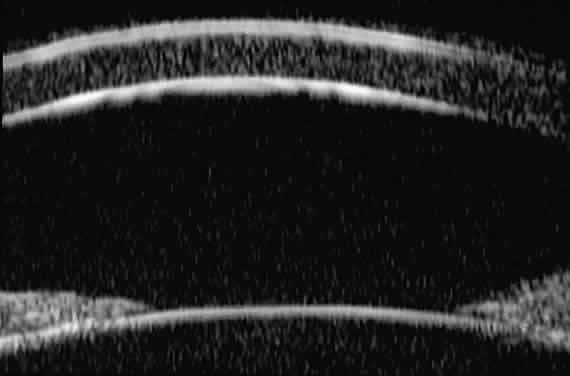

Ultrasound biomicroscopic slices through the mid-cornea and pupil (Fig. 3) show (1) the cornea, (2) the anterior chamber, (3) the lens, and (4) the pupillary zone of the iris. The cornea appears to have four well-differentiated layers. The epithelium is a thin, relatively bright (sonoreflective) layer. Just below that is Bowman's membrane, which appears as a highly reflective, very bright line. The stroma is the thickest layer and shows relatively homogeneous low-amplitude reflectivity. The endothelium and Descemet's membrane cannot be differentiated; together they form a single, highly reflective line at the posterior corneal surface. The aqueous in the normal anterior chamber appears completely sonolucent. The pupillary zone of the iris appears as two fingerlike structures consisting of a relatively sonolucent stroma and a bright posterior pigment epithelium. The anterior lens capsule appears as a bright retropupillary line. The normal anterior lens cortex appears nearly sonolucent.1–3

Fig. 3. UBM slice through mid-cornea and pupil of normal eye.

Radially oriented slices through the corneoscleral limbus (Fig. 4) show (1) the transition from cornea to sclera, (2) the anterior chamber angle structures, (3) the intermediate and peripheral zones of the iris, (4) the anterior ciliary body, (5) the equator of the lens, and, in some eyes, (6) the zonule. The corneoscleral junction is seen as an abrupt transition between the more sonolucent corneal stroma and the more sonoreflective sclera. The scleral spur can usually be identified as the most anterior extension of the deep sclera fibers at the limbus. The iris appears to consist of a relatively sonolucent stroma and a highly reflective pigment epithelium. The plane of curvature of the normal iris is smoothly bowed anteriorly. The insertion site of the iris relative to the scleral spur and anterior face of the ciliary body can be assessed. The pars plicata appears as fingerlike projections with acoustic features similar to those of the iris stroma. The ciliary sulcus is imaged between the peripheral iris and ciliary processes. The lens equator appears as a sonoreflective line (capsule) and underlying sonolucent stroma. Zonular filaments can be seen extending from the ciliary processes to the equatorial region of the lens in some eyes.

Fig. 4. Radial UBM slice through corneoscleral limbus of normal eye.